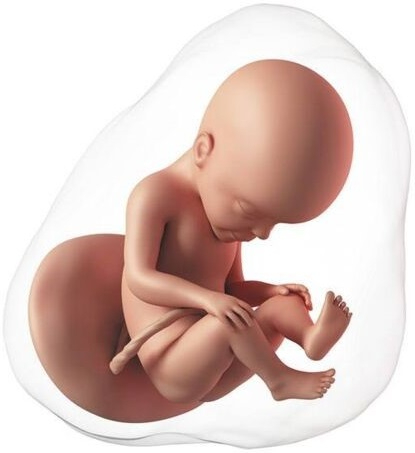

El embrión ya tiene forma de un pequeño cuerpo humano, mide aproximadamente 20 mm de cabeza a pies. En la cara se forman estructuras pequeñas como la retina y los párpados, el labio superior, la nariz y las orejas.

El cuerpo se va alargando, en las extremidades tiene unos surcos que darán lugar a los dedos. El embrión empieza a moverse, son los primeros movimientos involuntarios del embrión.